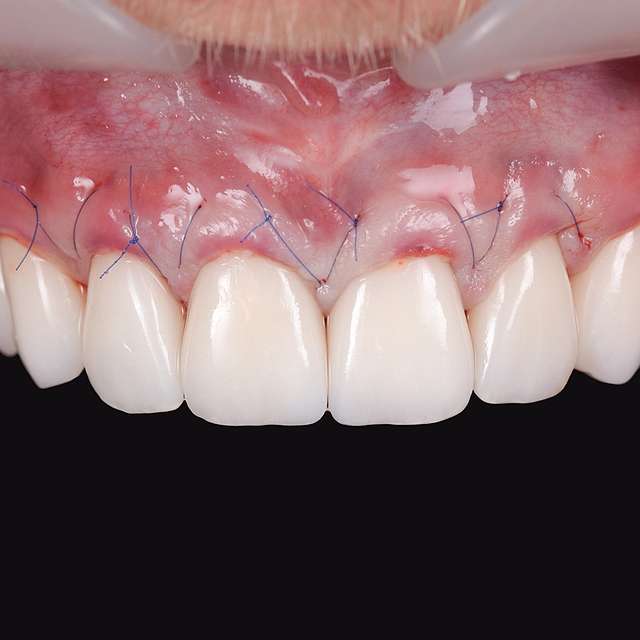

A gingival graft is a micro-surgery that will transplant a bulk of soft tissue - free gingiva or connective tissue ( the internal layer of gingiva ) to cover a soft tissue defect. Usually this type of procedures is required to augment implants, or to cover defects caused by periodontal disease or trauma. The grafts are harvested from the third molar region or the palate, and are transported where they are needed.

This type of procedure is a very delicate one, using the same type of blades like the ones used in ophthalmology and the sutures are also very thin. The sutures will be removed after 7-14 days, depending on the case, when primary healing is achieved. The maturation of the graft will take roughly 90 days, this is the reason why, when placing implants we prefer to also do the graft, so we can sync the healing time for both procedures.

Using tissue grafts to correct tissue defects

Using tissue grafts to correct gingival levels or cover recessions